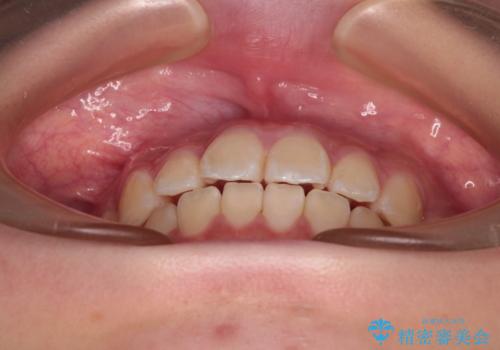

- 上下前歯のねじれを気にして来院された患者様です。

ワイヤー矯正でもマウスピース矯正でも対応可能でしたが、マウスピース矯正の自己管理が面倒であること、上顎前歯の捻転が著しいことから、ワイヤー矯正での治療を希望されました。

インビザライン治療が継続できない性別と年齢が世界的に調査されているそうですが、ほとんどの国で女子高生が最も多いとのことです。